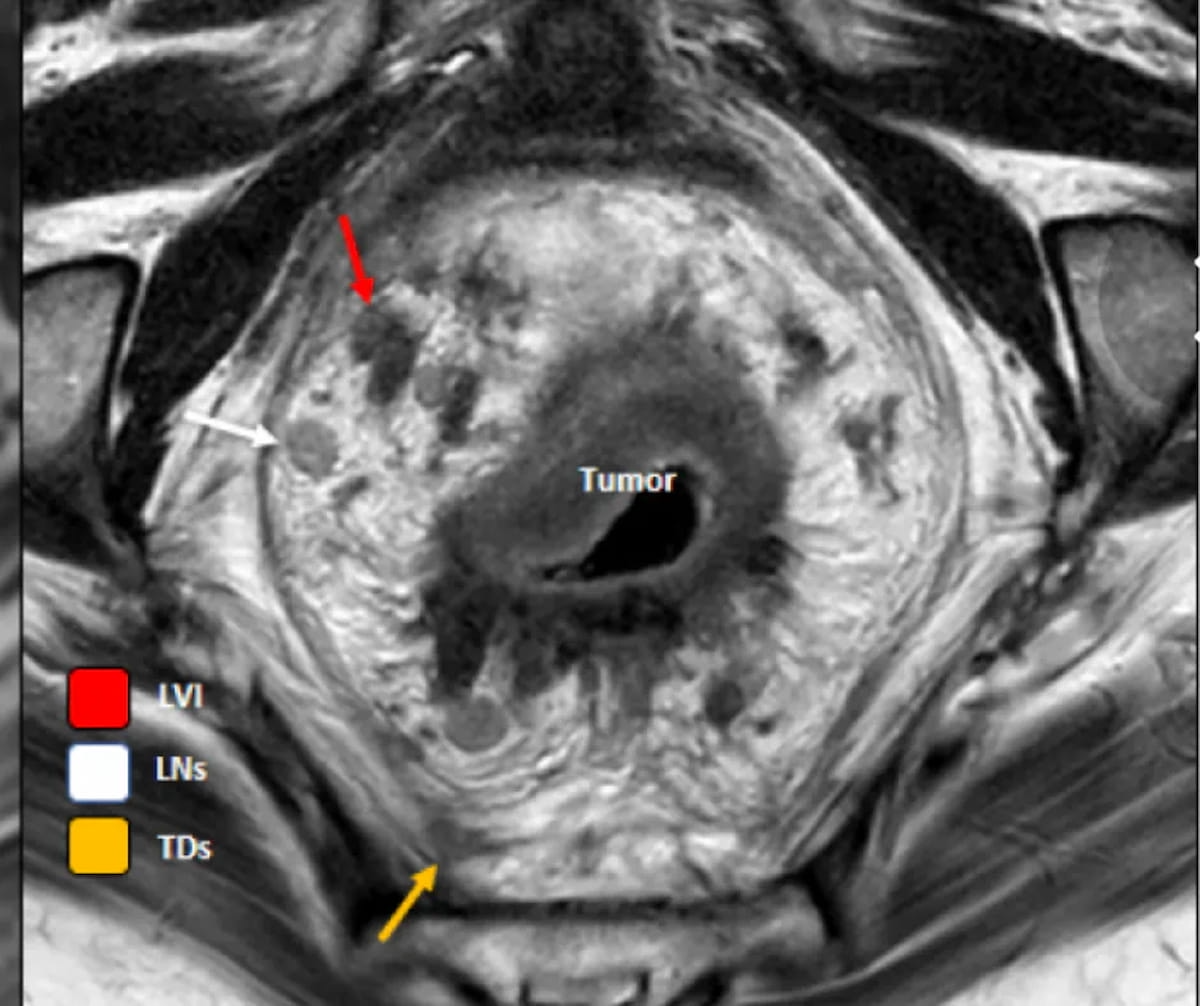

An emerging deep learning model, which incorporates T2-weighted MRI and clinical data, demonstrated an 83.9 percent AUC and an 85 percent specificity rate for preoperative prediction of tumor deposits in patients with rectal cancer.

In one of the study periods from recently published research on rectal MRI acquisition, researchers found that 39.7 percent of rectal MRI exams adhered to guidelines from the Society of Abdominal Radiology (SAR) and only 6.8 percent followed guidelines from the European Society of Gastrointestinal and Abdominal Radiology (ESGAR).